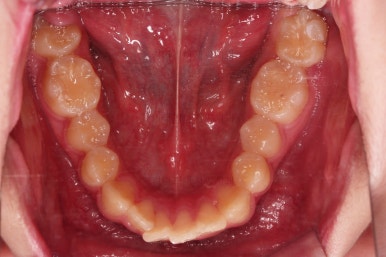

치료 끝!

전체적인 교정을 하지 않았기 때문에 완벽히 디테일을 맞추긴 힘들었지만 충분히 기능을 할 수 있게끔 위치를 바로잡아 주었어요.

총 치료기간은 단 5개월!

부산연산동사랑니발치 치료 전후를 비교해 보겠습니다.

5개월이라는 매우 짧은 기간인데 정확한 치료계획과 고난이도 테크닉으로 매복 사랑니도 발치하고 매복된 어금니도 바로 세워서 잘 사용할 수 있게끔 해드렸습니다.